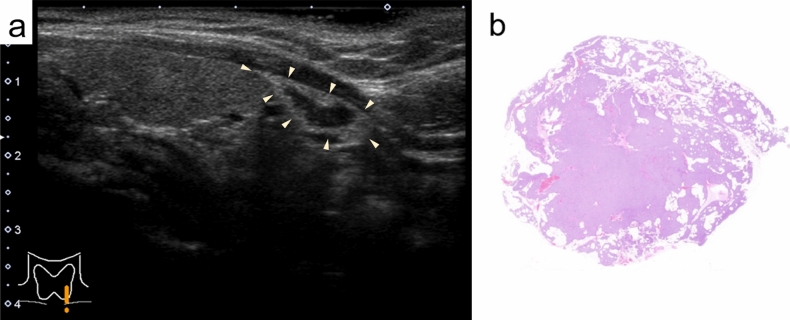

Results: Ultrasonography revealed a lipoadenoma detection rate of 20.0%. This increased to 80.0% at re-examinations performed after obtaining information from other imaging modalities. Compared with parathyroid adenoma cases with no adipocytes or few adipocytes, the frequencies of ill-defined margins, iso- and/or hyperechogenicity, heterogeneous consistency with a two-tone pattern, poor vascular flow, no polar artery, and no hyperechoic line were significantly higher in parathyroid lipoadenoma cases. The hyperechoic and isoechoic areas in tumors with a two-tone pattern correspond to adipocyte- and parathyroid cell-rich areas, respectively. The lipoadenoma tumor sizes measured using ultrasound tended to be smaller than the actual sizes.

Abstract Image